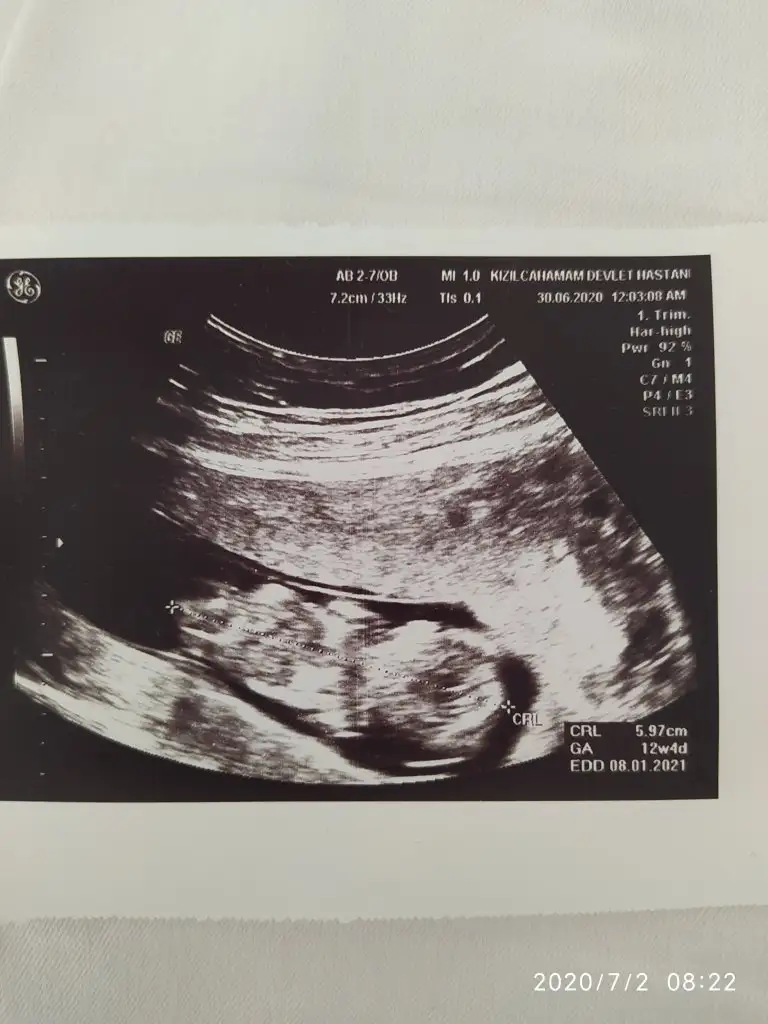

En iyi 11 12 13 şimdilik erkek kese konumuAnlayanlar bunada bir yorum yapabilir misiniz acaba

Biliyorum belki çok erken ama merak işte 9 haftadayım herhangi bir tahmin yapabilir misiniz

Evet sırt dönük başka yokmu tipi kız sanki ama tutmayabilir nuba bakmadım

Doktor %50 tahmin ederim dedi istemedik ağustosta tam net söylicek inşallahErkek gibi sanki

Hıım tmm cnm zaten 12-13 haftalıkken gideceğim ozamanda paylaşırım :) yorumladığın için saol :)En iyi 11 12 13 şimdilik erkek kese konumu